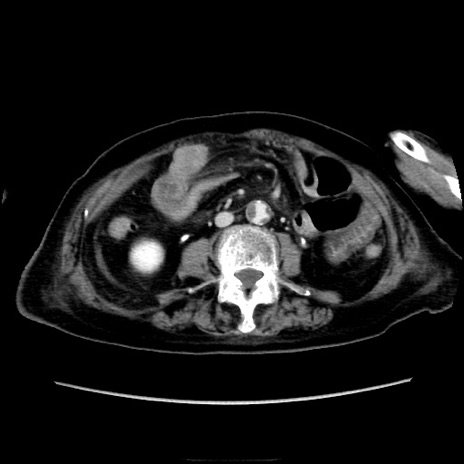

症例40(横断像)

【症例】90歳代女性

【主訴】腹痛・嘔吐

【現病歴】 食欲低下、嘔吐があり昨日他院受診。肺炎と診断され入院となる。入院後より腹部全体に圧痛あり。胃管留置され経過みていたが、症状持続するため、

当院転院となる。

【既往歴】胸椎圧迫骨折、胆石症

【身体所見】腹部:中央に激痛あり、圧痛あり、反跳痛不明

【データ】WBC 17100、CRP 18.82

横断像